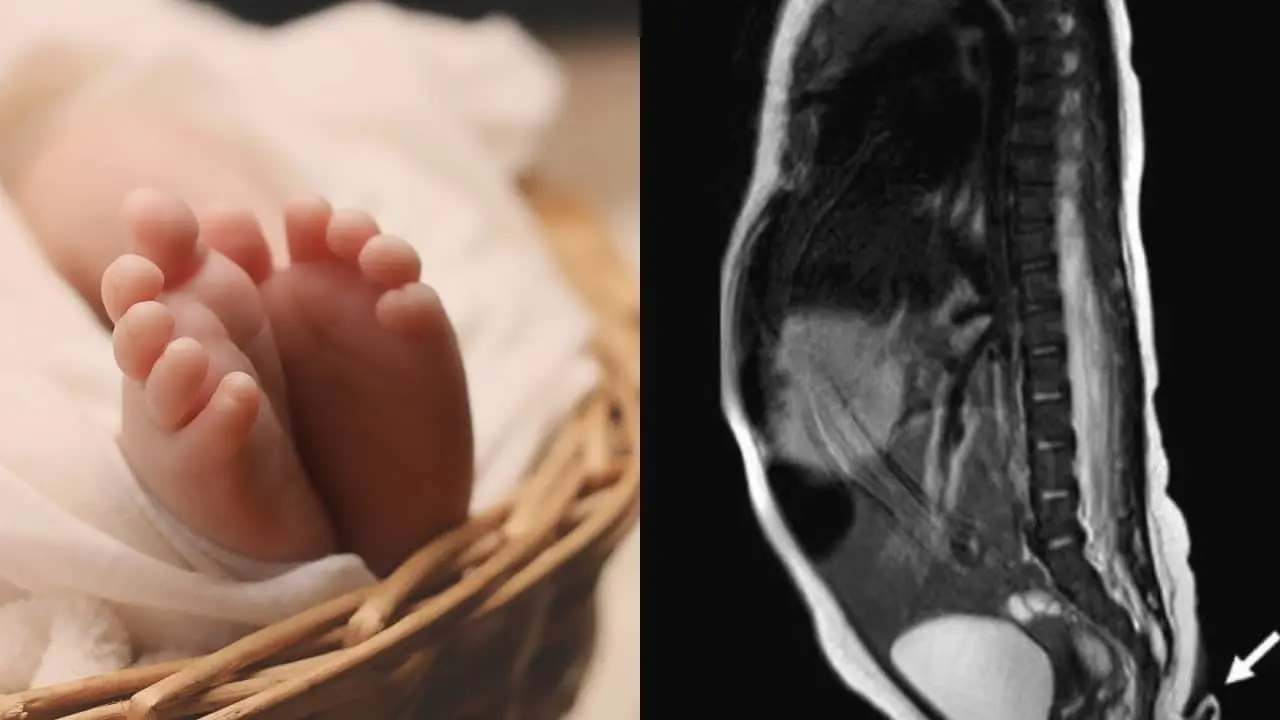

De acuerdo con los especialistas, existen dos tipos de colas humanas; las ´psudocolas´, mismas que son crecimientos que se asemejan a una cola pero que se originan en la columna vertebral o tumores y las ´colas verdaderas´, son las que contienen músculos, vasos sanguíneos y nervios, aunque no huevos.

En el caso del bebé que nació en Nuevo León, su cola tiene carne con tejido blando, arterias, venas y haces de nervios. Tras dos meses, los médicos volvieron a examinar a la pequeña y se percataron de que la cola había crecido y fue entonces cuando determinaron que debían extirparla, lo cual no presentó complicaciones.